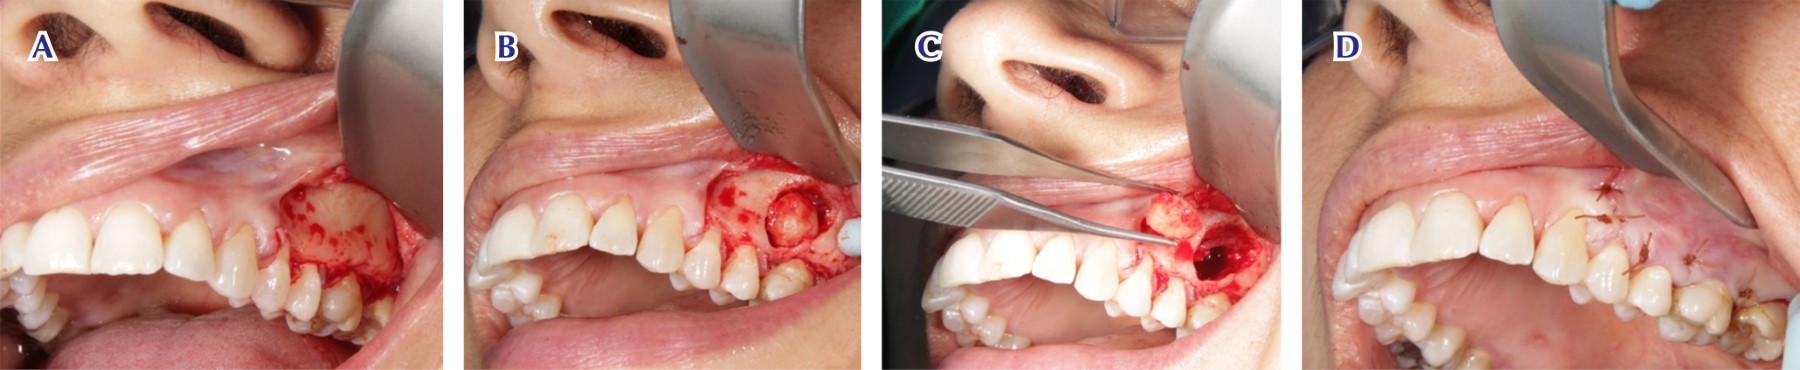

Figure 2